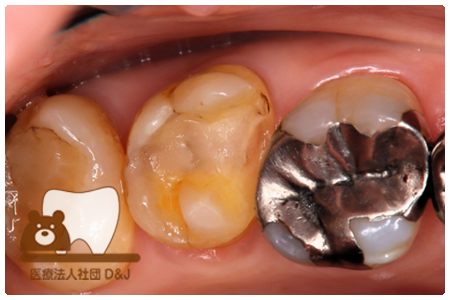

症例8フルジルコニアクラウン

治療前

治療中

治療後

29歳 女性

- 治療内容

- 銀歯からフルジルコニアクラウンへの修復

- 治療期間

- 根の治療含め3か月

- 費用

- 自費

フルジルコニアクラウン:77,000円(税込)

- その他の治療の費用は含まれておりません。

- リスク・副作用

- 強い衝撃が加わると欠けたり割れたりする可能性があります。また、噛み合わせの状態によっては脱離や周囲の歯への影響が出ることもあります。